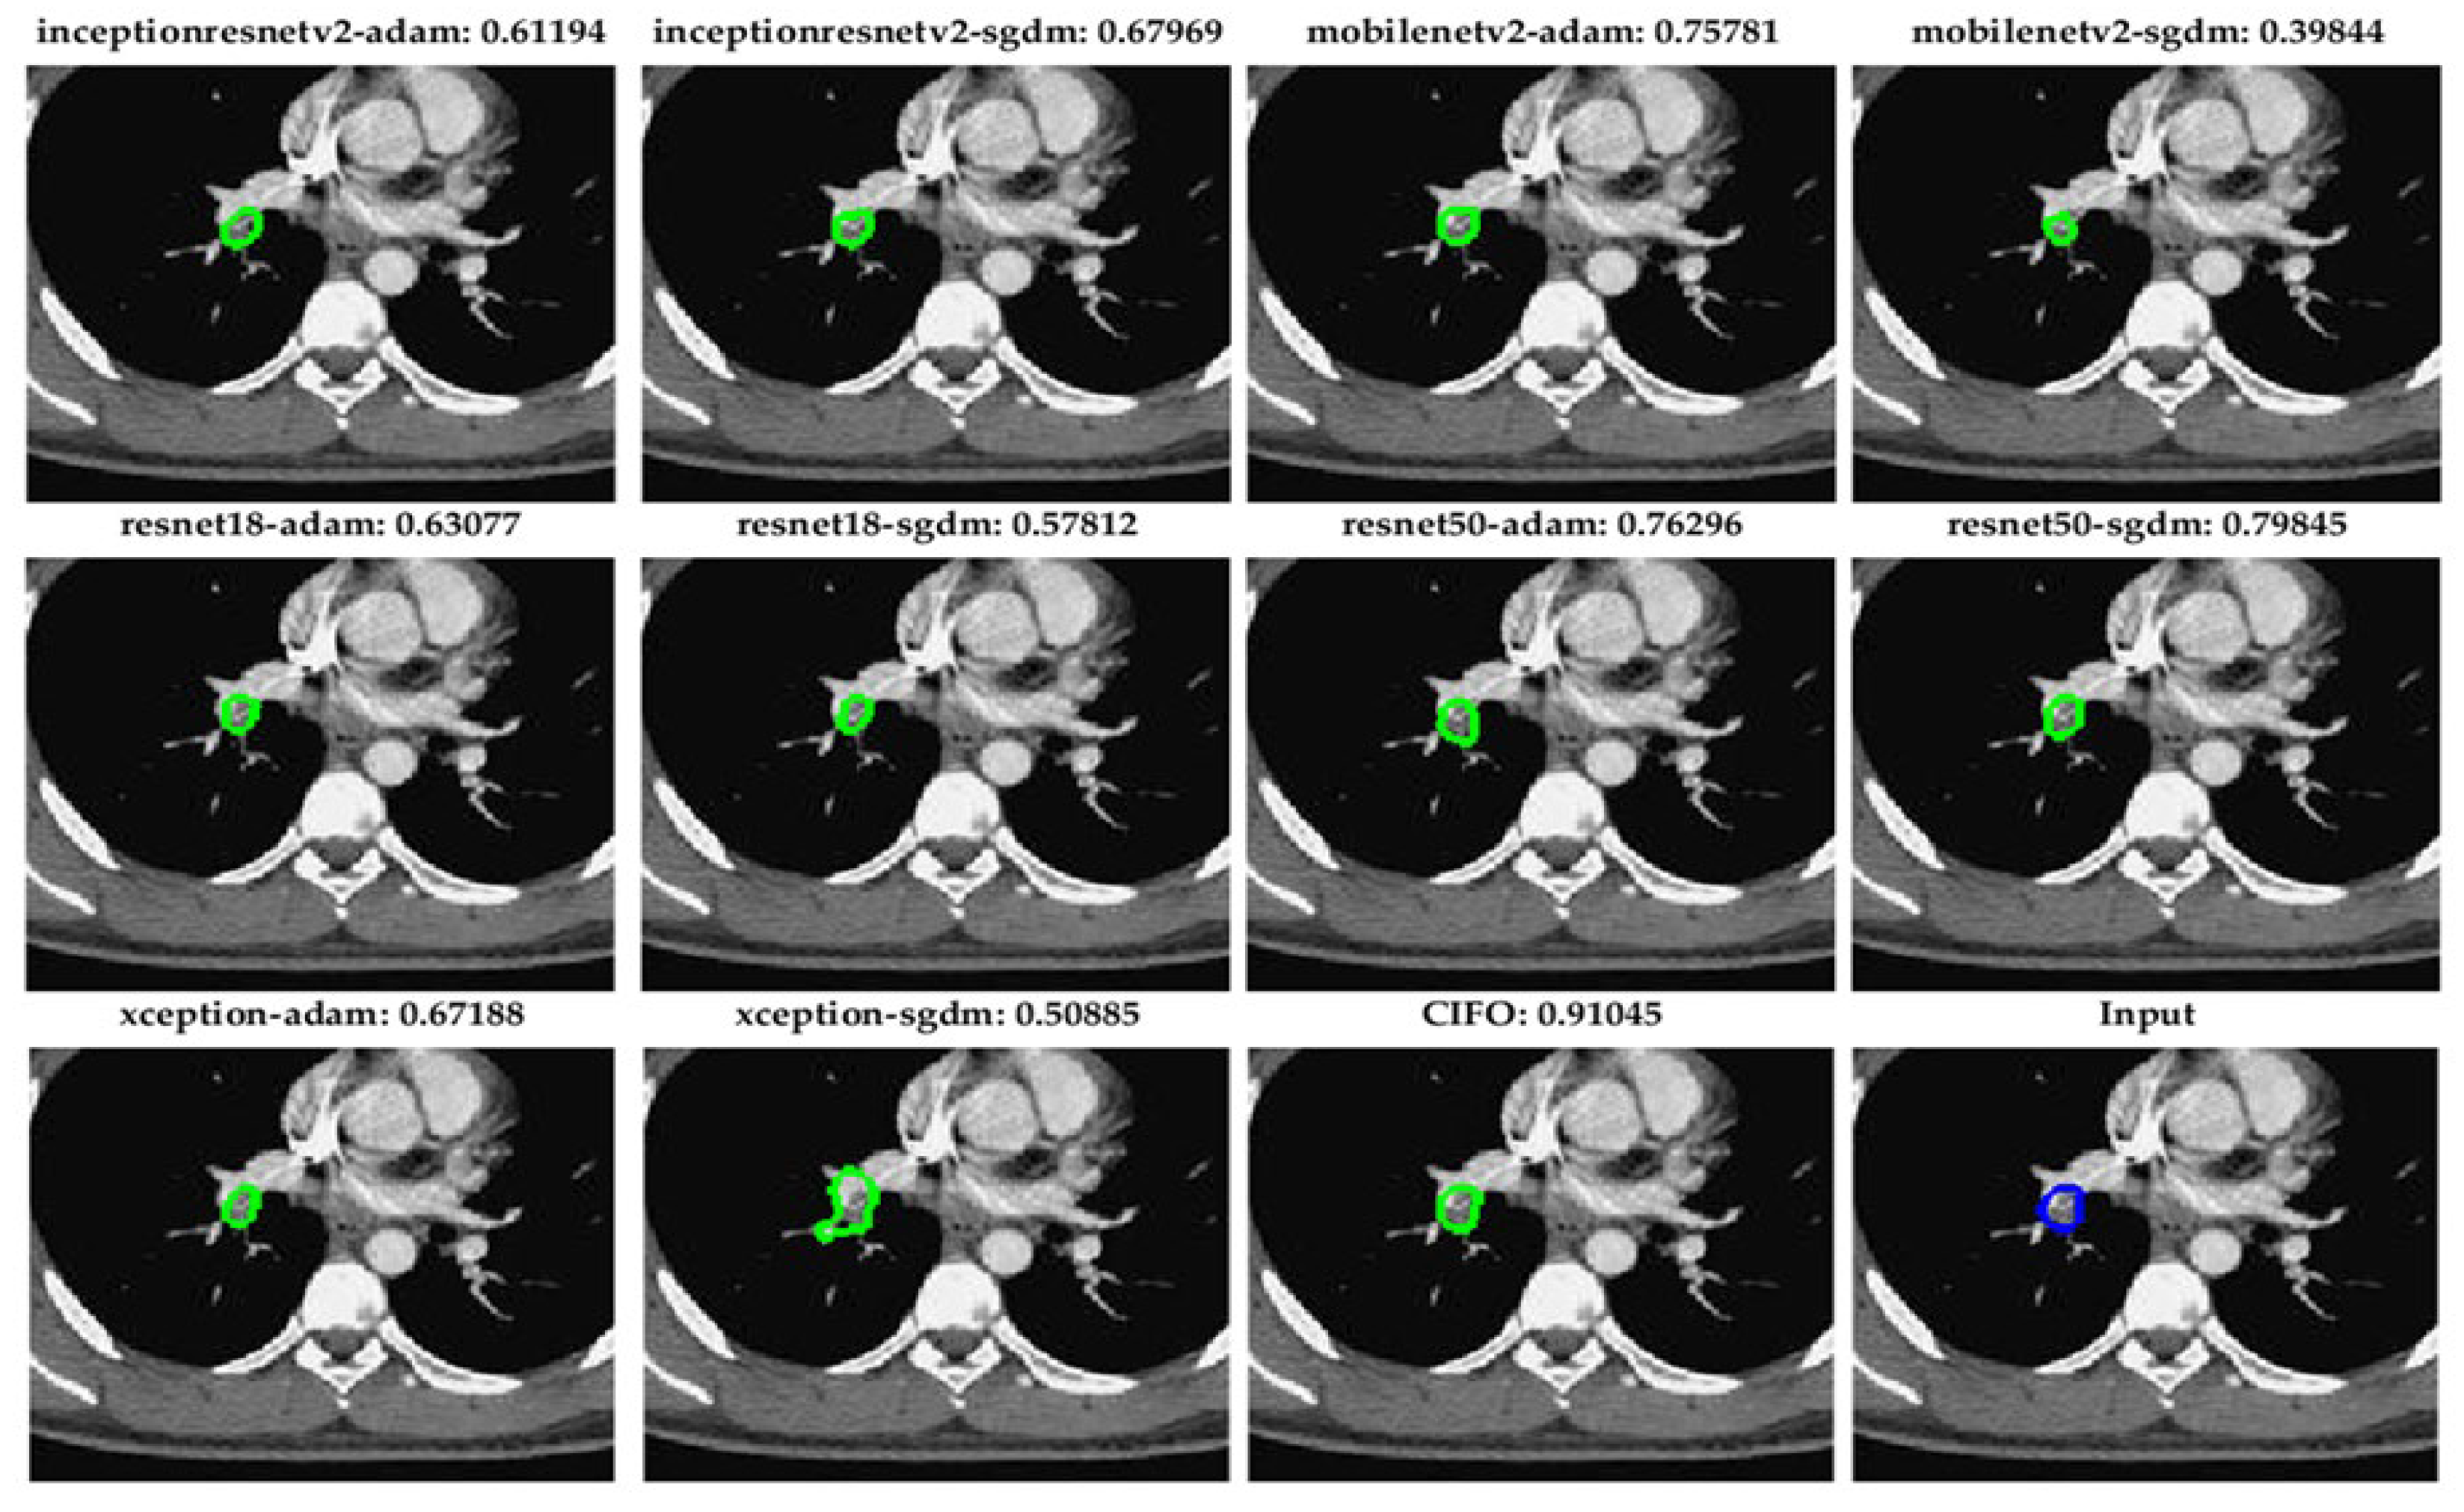

5.2. Robust Segmentation of Subsegmental Emboli with CIOF Fusion

Figure 6 demonstrates segmentation outcomes of small pulmonary emboli (<26 pixels) across ten fully convolutional network (FCN) configurations and the CIOF ensemble method. Each sub-image includes the original CTA slice with overlaid segmentation results. The Dice similarity score is displayed above each panel. The CIOF method demonstrates superior performance (Dice: 0.91045) compared to individual models. CIOF consistently provides a more accurate and complete delineation of emboli compared to individual models, especially in challenging small-vessel regions.

Accurate segmentation of small pulmonary emboli (<26 pixels) is crucial due to their clinical and technical significance. Clinically, these small emboli often reside in distal or subsegmental arteries, serving as early indicators of pulmonary embolism (PE) and enabling timely intervention to prevent progression and improve outcomes. Technically, their low contrast and limited size make them challenging to detect, often resulting in high false-negative rates in individual models. The proposed CIOF fusion method addresses these challenges by integrating outputs from multiple FCN models, enhancing consensus and robustness in identifying subtle embolic regions. This adaptive ensemble approach improves sensitivity and reliability, especially in small-vessel territories where traditional models may fail.